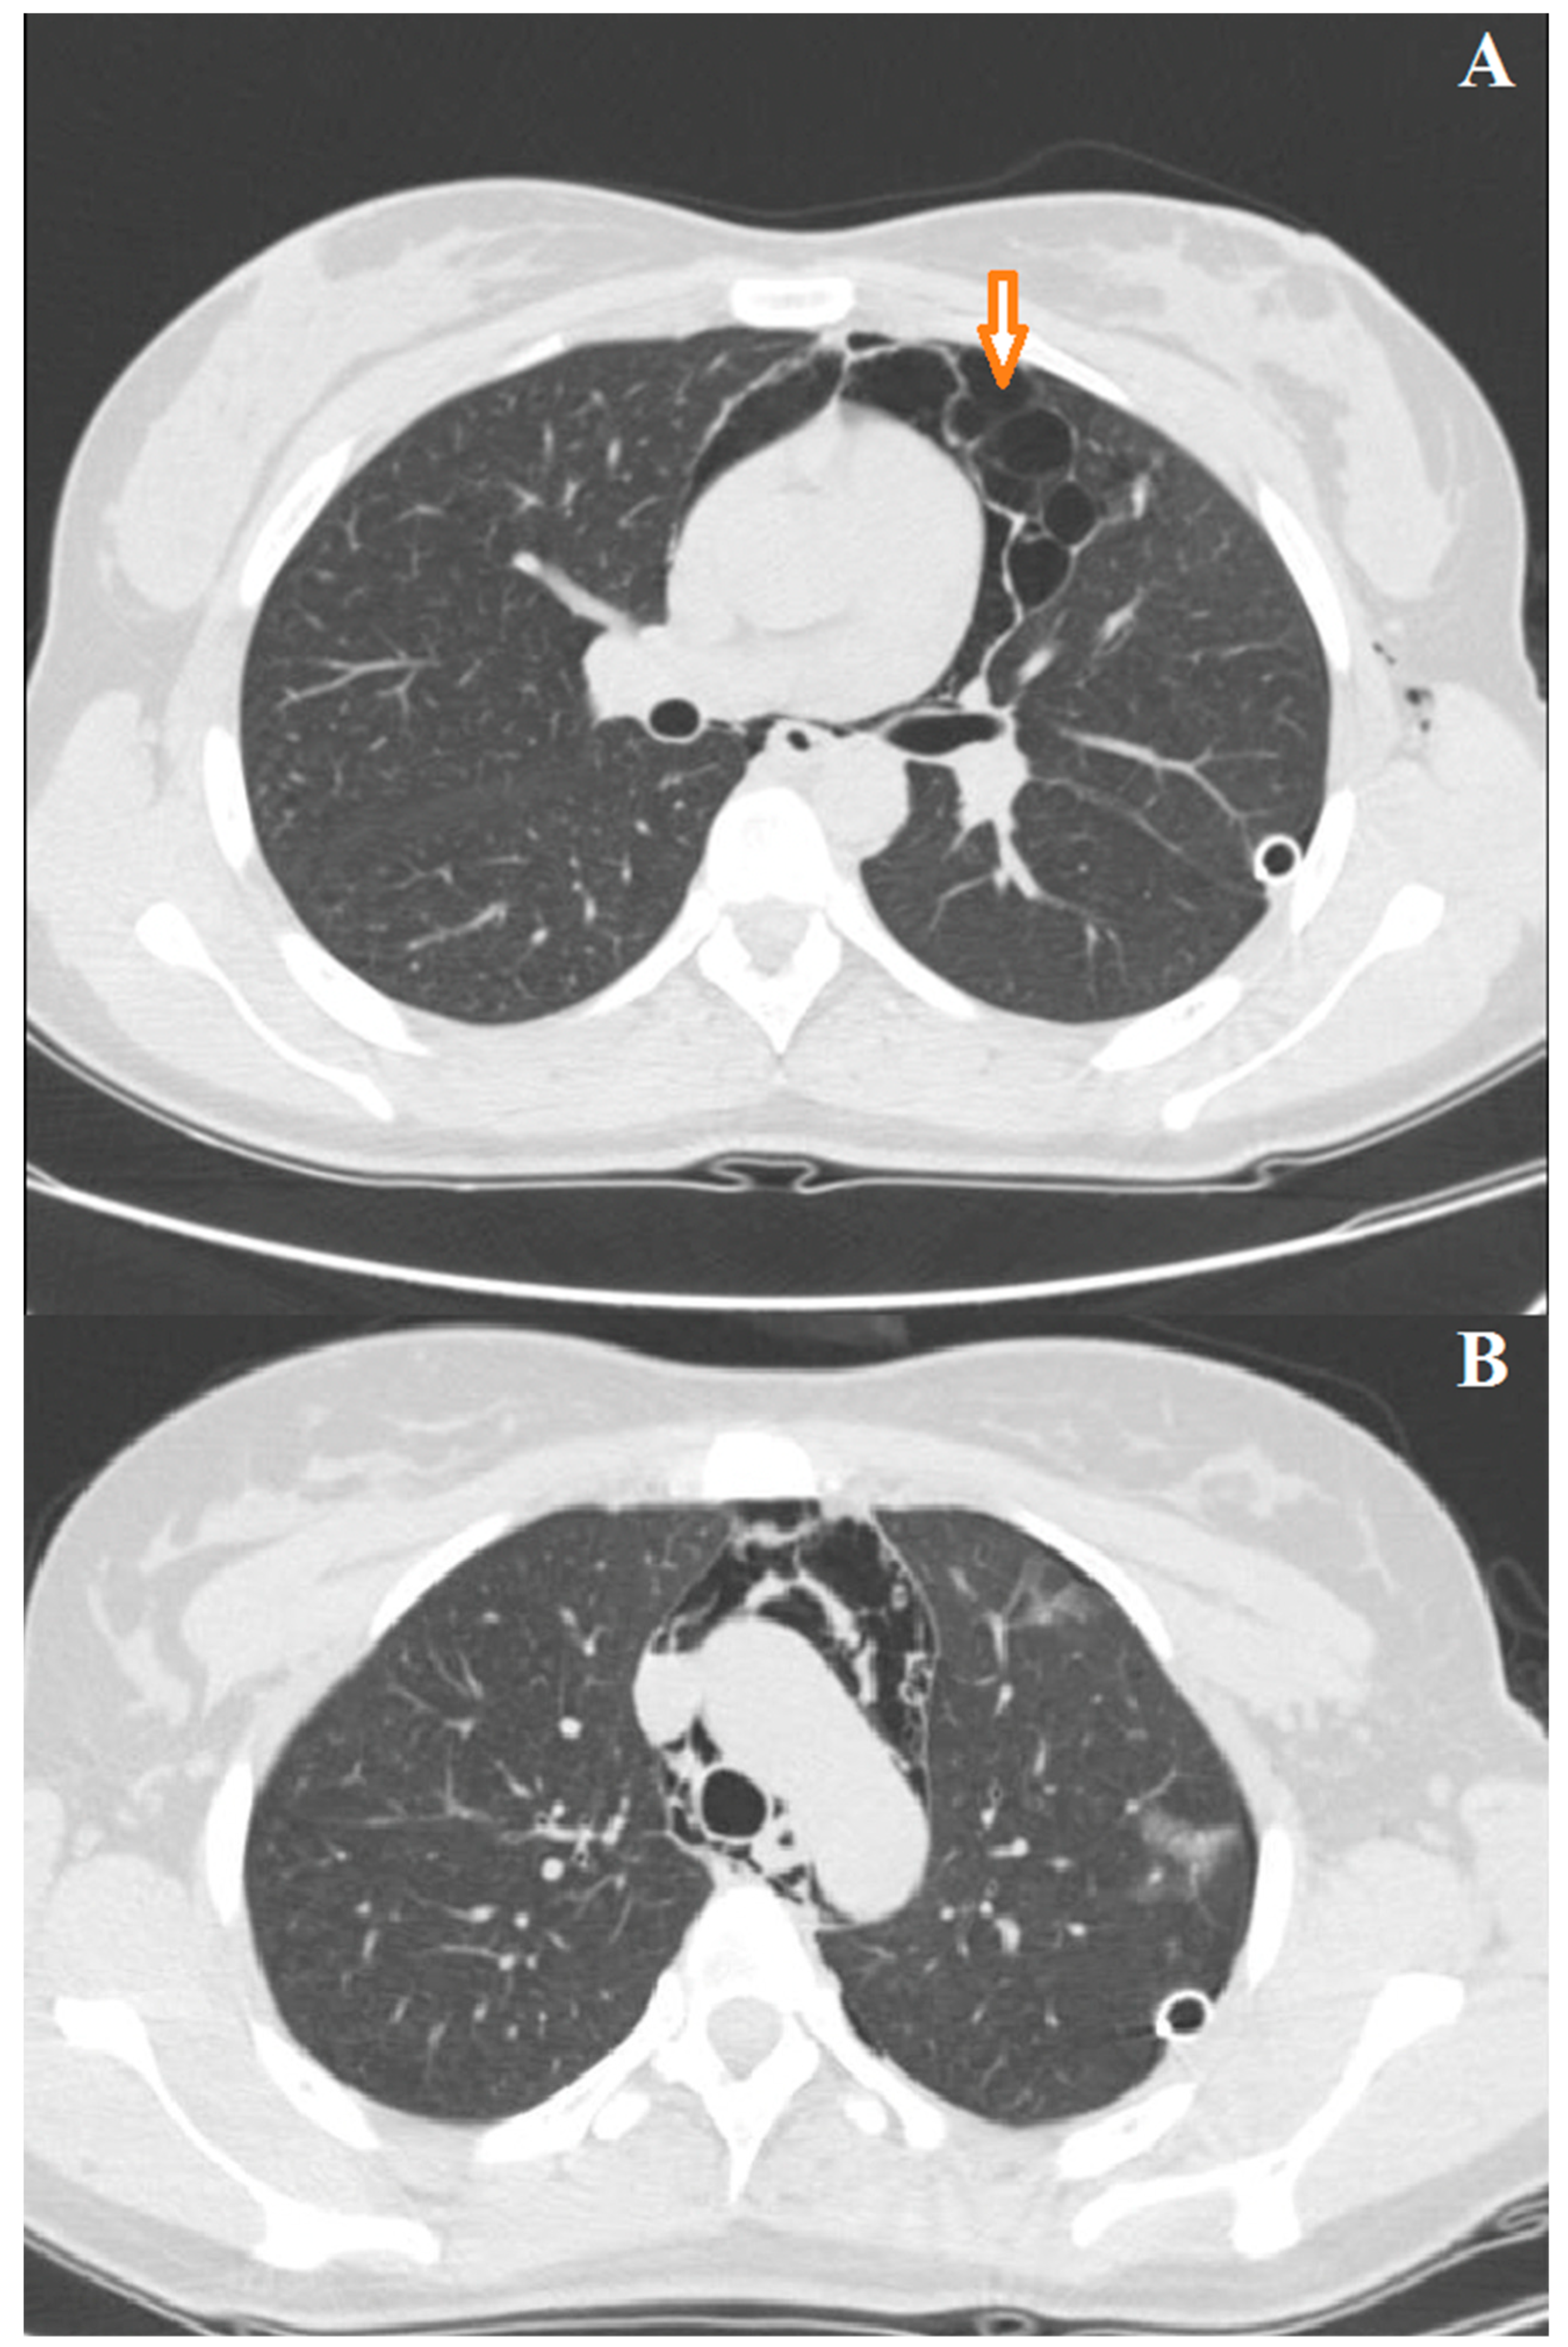

3.1. Case 1

3.2. Case 2

3.3. Case 3